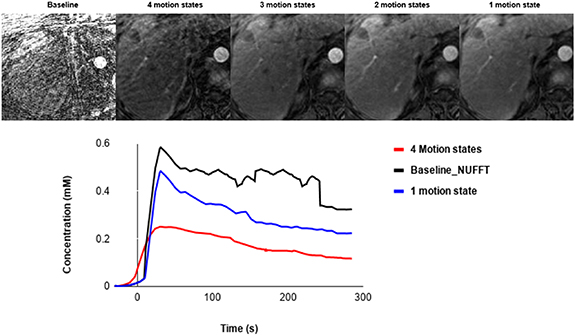

Standard image High-resolution imageFigure 7. Example of XD-GRASP with different number of motion states and a baseline approach and the corresponding aorta concentration.

Compared to the baseline reconstruction, we can clearly see the importance of XD-GRASP with regards to quality image as shown in figure 7. This reference reconstruction was evaluated using the same ROI and same length of time points to generate the corresponding perfusion curves and compared it to GRASP and XD-GRASP. There is a significant difference between the baseline and the images reconstructed with XD-GRASP, particularly concerning image quality, and shows higher peak of aorta concentration, but is more noisy and unstable.

The concentration increases by reducing the number of motion states. Therefore, the images reconstructed with 1 and 2 motion states show the highest concentration for the enhancement arterial curve (≈0.5 mm and 0.3 mm respectively) with higher temporal resolution. While those reconstructed with 3 and 4 motion states were almost the same by representing a lower concentration (≈0.25 mm) of the unclear arterial enhancement peak due to the lower temporal resolution.